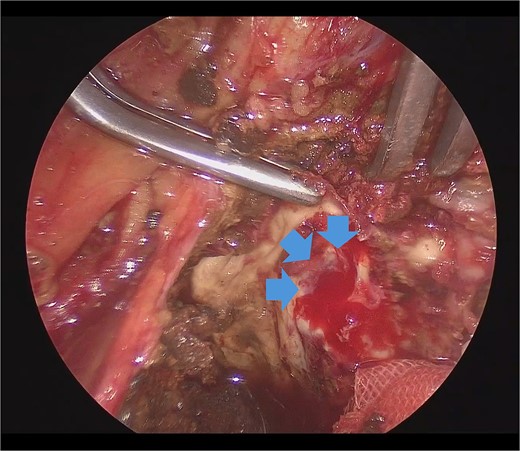

He underwent surgery under general anesthesia. A midline abdominal incision and an intraperitoneal approach were employed. Due to the aneurysm’s size, combined with adhesions to the surrounding intestines and the thinness of the aneurysm wall, achieving complete exposure was particularly challenging. Therefore, the aneurysm was incised midway. The hematoma and coils were removed, and the feeding vessels were ligated with 3–0 monofilament. Blood oozing from the feeding vessels suggested that the aneurysm expansion was likely due to a type II endoleak that was not visible on contrast-enhanced CT. The laparoscope was used to observe the aneurysm, identify, and ligate the inflow vessels that were difficult to visualize directly (Fig. 2). The IIA was sutured with 3–0 monofilament using laparoscopic assistance, taking care to avoid including adjacent structures such as the rectum in the sutures. The operation took 255 min, and the patient was discharged on the fourteenth day postoperation. Follow-up CT at 10 months postoperation showed a reduction in aneurysm size (Fig. 3).

Laparoscopic view of the orifice of the feeding vessel (blue arrow).